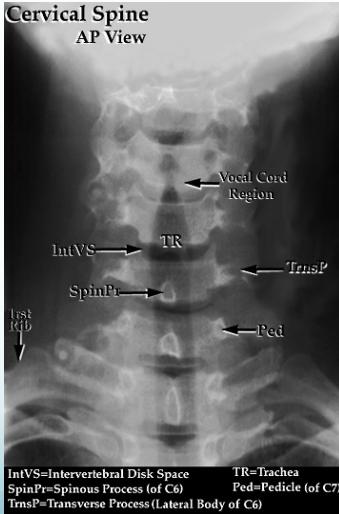

X-rays for C-Spine Injuries

AP View

- Intact lateral outline

- Spinous processes & Trachea in the middle

Key Anatomical Landmarks:

- IntVS = Intervertebral Disk Space

- SpinPr = Spinous Process (of C6)

- TrnsP = Transverse Process (Lateral Body of C6)

- TR = Trachea

- Ped = Pedicle (of C7)